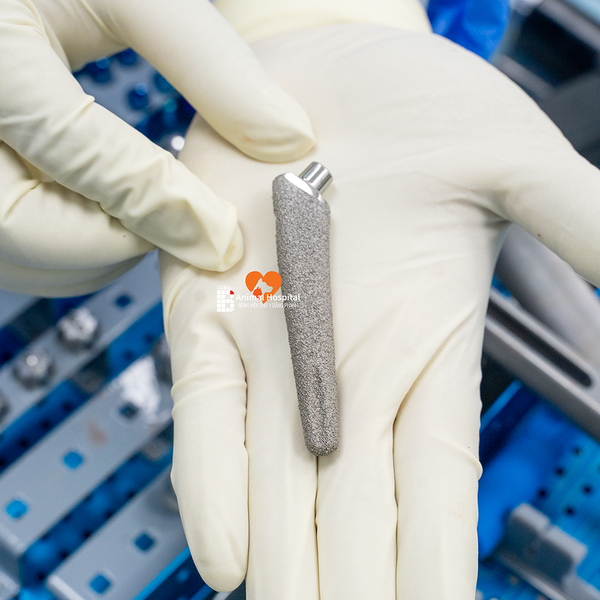

⚙️ Cấu hình sử dụng | Implant Configuration

- Chỏm đùi: PEEK 20mm

- Cup acetabulum: Titan không xi măng 25mm

- Thân femur: Không xi măng size #8

- Cổ xương: Size 0

- Ốc bên: 22mm cố định cup